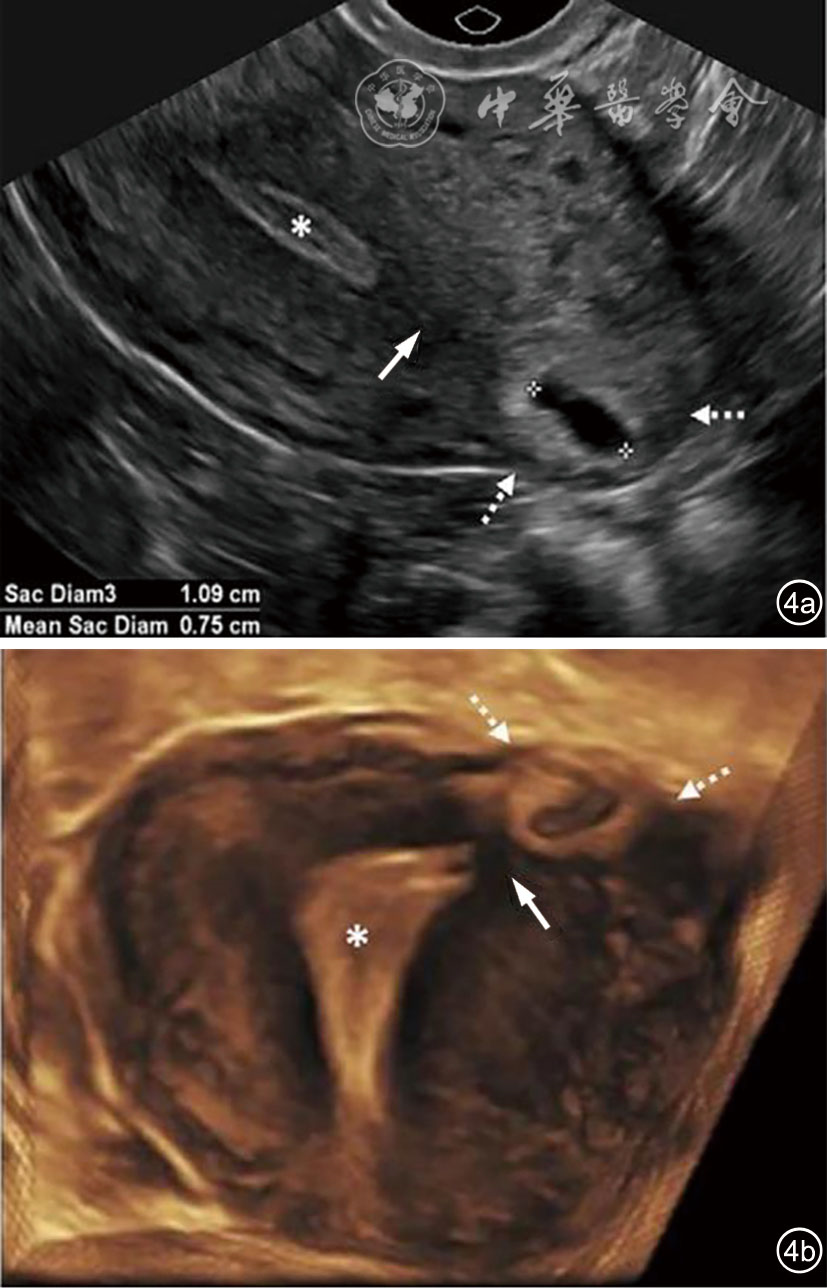

2.输卵管间质部异位妊娠:输卵管间质部异位妊娠较罕见,指受精卵着床于输卵管间质部(嵌入子宫肌壁内的输卵管近端部分)(图4)。超声诊断要点包括:(1)子宫与妊娠囊间滑动征阴性;(2)三维冠状切面重建图像显示子宫肌层部分包绕妊娠囊(妊娠囊周边子宫肌层组织呈“爪形征”),或子宫内膜与妊娠囊间可见薄层肌层组织;(3)间质线征仅偶见(图5),但该征象诊断输卵管间质部异位妊娠特异度较高。应避免使用‘宫角妊娠’或‘宫角异位妊娠’。

图5 间质线征超声图像。图为33岁孕妇(孕6周0天)经阴道超声横切面灰阶图像,显示右侧输卵管间质部异位妊娠(实线箭头)。除输卵管间质部异位妊娠特征性超声表现外,另可见一纤细高回声线(虚线箭头)连接子宫内膜与异位妊娠囊,为“间质线征”(图5译自参考文献[1])